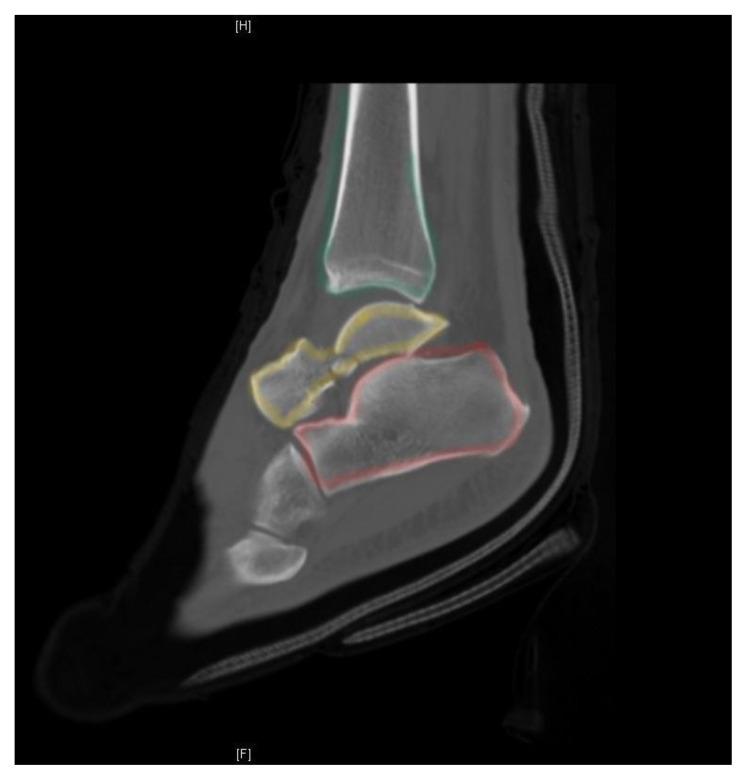

Case Report: Talar Neck Fracture.

This report demonstrates a case of a severe talar neck fracture. Although rare, talar neck fractures have a high potential for morbidity. Typically caused by a high energy injury, this patient's mechanism of injury was relatively minor, and presentation was not immediately concerning for such a severe fracture. Initial x-rays provided a gross demonstration of the fracture, but a CT scan was obtained to better evaluate the bone fragments and associated tarsal dislocations. The patient was treated symptomatically and splinted in the emergency department, underwent open reduction and internal fixation the next morning, and was discharged a day later. The patient's severe injury was identified and received definitive treatment to help avoid potentially devastating complications.